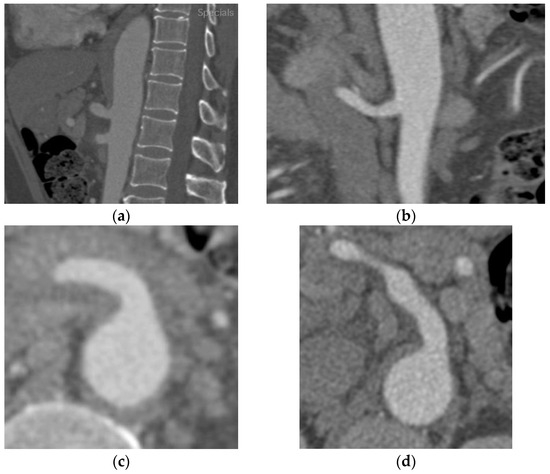

2.2. Case B